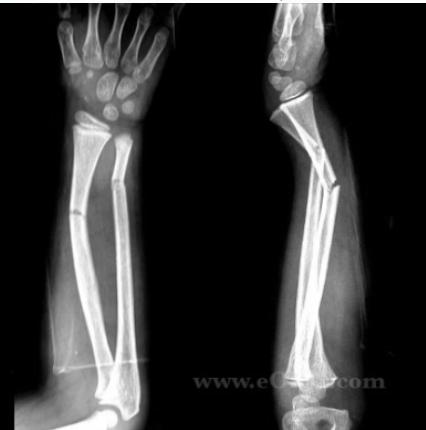

Intramedullary Elastic Nail

- 2 fractures at the same level = 100% unstable

- When unstable or re-displaces in cast